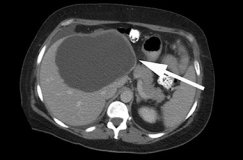

Обнаружена киста на печени, но причины ее возникновения не установлены? Что в таком случае делать? Для начала необходимо обратиться к врачу для назначения обследования организма, это поможет быстрее понять причину появления опухоли в печени. Чаще всего для диагностики любого заболевания, лечащие врачи назначают УЗИ брюшной полости. Благодаря такой диагностике внутренних органов можно установить размер опухоли, ее месторасположение, количество, область поражения, а также определить разновидность жидкости. В последнем случае УЗИ выступает контрольным методом проведения прокола опухоли (лапароскопия).

Также не уступает УЗИ и КТ (компьютерная томография), которая назначается для определения точного размера кисты. МРТ (магнитно-резонансная томография) позволяет еще и установить причину возникновения опухоли в печени.